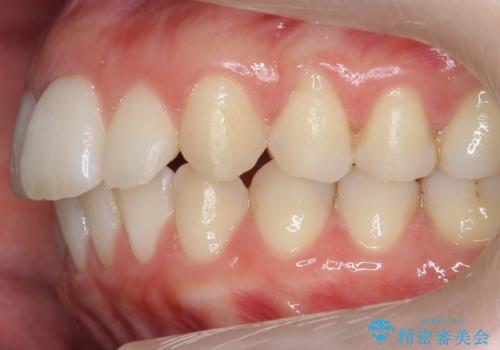

- 表面の着色を気にされて、ご来院されました。

お話しをしたところ、リーズナブルに短時間で綺麗にしたいとの事でした。

そこでPMTCの30分コースで、目立つ部分を中心に落としていきました。

タバコのヤニ・茶渋などの歯の着色除去は、保険適用外になります。

当院ではブラシ・クリームで研磨するPMTCに加え、

細かい所まで着色除去できるエアフローも取り揃えておりますので、